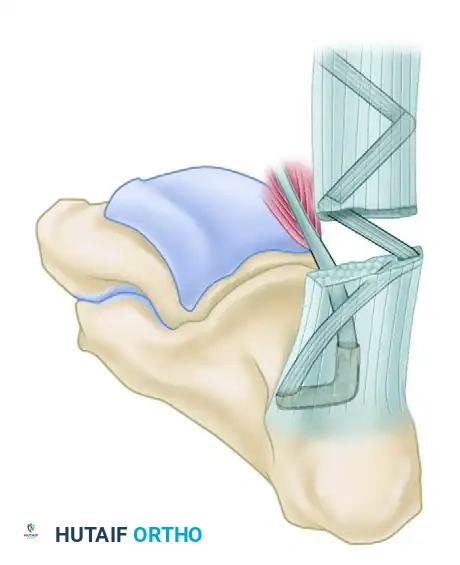

Phase 3: Calcaneal Tunnel Preparation

- Transverse Drill Hole: Drill a transverse hole just deep and distal to the insertion of the Achilles tendon, passing halfway from medial to lateral through the calcaneal body.

- Vertical Drill Hole: Drill a second hole vertically, starting just deep to the Achilles insertion, directed plantarward to intersect the first transverse drill hole midway through the posterior calcaneus.

- Tunnel Dilation: Enlarge the intersecting tunnel using a large towel clip or a specialized tendon passer to ensure smooth passage of the FHL graft.

Phase 4: Tendon Weaving and Fixation

- Tendon Passage: Using a suture passer, pull the tag suture of the FHL through the calcaneal tunnel from proximal to distal, exiting the transverse hole.

- Tensioning: Place the ankle in approximately 15 degrees of plantar flexion to set the appropriate resting tension.

- Weaving: Pass the FHL tendon through the tunnel, then route it proximally. Weave the FHL tendon from distal to proximal through the remaining substance of the Achilles tendon (or the aponeurosis) using a tendon weaver. Continue weaving until the full length of the harvested FHL tendon is utilized.

- Securing the Construct: Secure the weave at multiple points using heavy, non-absorbable sutures (e.g., 1-0 Dacron or FiberWire).